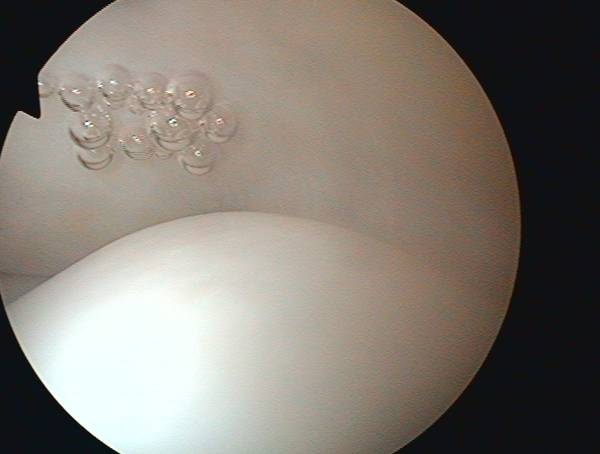

oben: intakte Rotatorenmanschette, unten: gesunder Knorpel des Oberarmkopfes